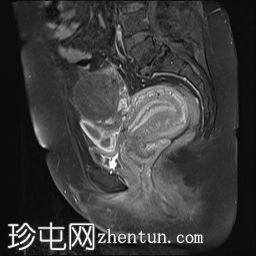

矢状位

T2加权像

可见子宫外腹腔内妊娠囊,内含胎儿组织。

该妊娠囊向后推移子宫,并与剖宫产瘢痕凹陷处紧密相连。

该妊娠囊与相关肠袢无法分离。可见其与性腺血管密不可分,且性腺血管明显突出。

胎盘位于妊娠囊后方,紧贴子宫前壁。

沿妊娠囊下缘可见一处异质性局灶性积液,最大轴向尺寸约为 8.4 × 5.5 cm,T1 加权像呈异质性高信号,T2 加权像呈异质性中等信号,T1 脂肪抑制序列未见信号下降,提示为血液成分。该积液压迫膀胱。

可见周围脂肪间隙呈条索状改变。

左侧卵巢无法辨认。

右侧卵巢未见实性或囊性肿块。

子宫体积增大,后倾,子宫内膜厚度约 1 cm,子宫下段前壁可见局灶性变薄(既往子宫瘢痕)。子宫连接区完整,未见肌层肿块。可见子宫内膜腔边缘有血性分泌物。